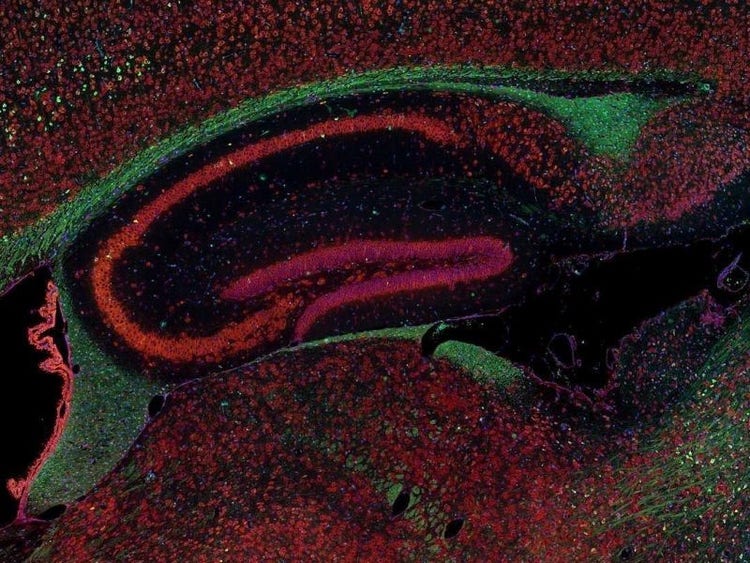

Fluorescence imaging of a mouse brain

각 확대 이미지는 특이해 보이지만, 모두 모아보면 형광 이미징으로 촬영한 생쥐 뇌가 나타납니다.

영국 과학자 George G. Stokes 경은 형석에 자외선을 비추면 형광을 발한다는 사실을 처음으로 목격했고, ‘형광’이라는 단어를 만들어냈습니다. Stokes 경은 형광 광원이 여기광원보다 파장이 더 길다는 사실을 발견했으며, 이 현상은 현재 스토크스 이동으로 알려져 있습니다. 형광 현미경은 자연적인 형태(일차 형광 또는 자가형광)이거나 형광을 발할 수 있는 화학물질로 처리했을 때 형광(이차 형광)을 발할 수 있는 물질을 연구하는 탁월한 방법입니다.